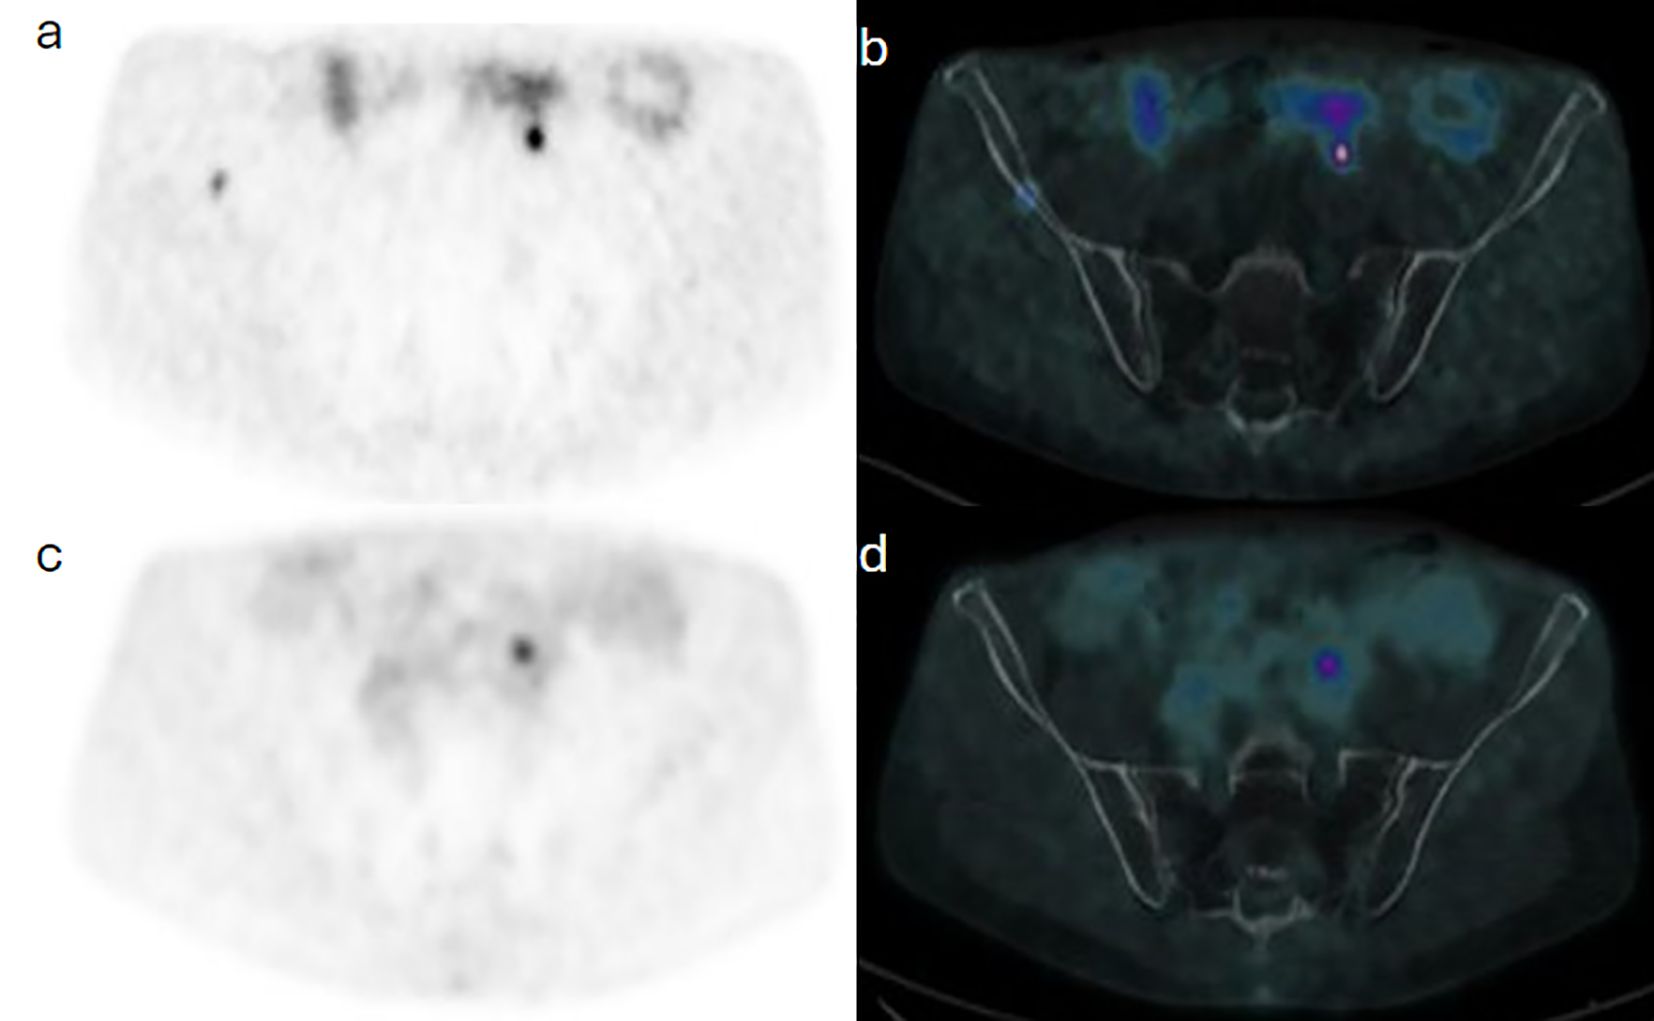

Background: Head and neck paragangliomas (HNPGs) are rare neuroendocrine tumors originating from neural crest cells, with some exhibiting malignant potential. Traditional imaging modalities, such as magnetic resonance imaging (MRI), often have limitations in detecting multifocal or metastatic disease, driving interest in more sensitive diagnostic approaches like Gallium-68 DOTATATE positron emission tomography/computed tomography (Ga-68 DOTATATE PET/CT). Methods: This retrospective study aimed to assess the effectiveness of Ga-68 DOTATATE PET/CT in the detection and management of HNPGs. Imaging data from 2015 to 2024 were reviewed, identifying four confirmed cases of HNPG. All patients underwent head and neck MRI and Ga-68 DOTATATE PET/CT scans. Data on imaging findings, treatment history, and clinical outcomes were collected and analyzed to compare the performance of Ga-68 DOTATATE PET/CT with other imaging techniques, including Iodine-123 meta-iodobenzylguanidine (I-123 MIBG) scintigraphy and Fluorine-18 fluorodeoxyglucose (F-18 FDG) PET/CT. Results: Ga-68 DOTATATE PET/CT demonstrated enhanced sensitivity in detecting both primary and metastatic lesions compared to MRI and other imaging modalities. It identified additional lesions not seen on MRI, confirmed local recurrence, and detected unsuspected metastatic sites, influencing clinical management. While Ga-68 DOTATATE PET/CT provided more diagnostic clarity than I-123 MIBG in one case, it also revealed additional metastatic sites in a patient with a succinate dehydrogenase (SDH) gene mutation, which were not detected by F-18 FDG PET/CT. Conclusion: Ga-68 DOTATATE PET/CT is a valuable imaging tool for evaluating HNPGs, with superior sensitivity in detecting both primary and metastatic lesions compared to conventional imaging. Its diagnostic advantages can significantly impact treatment planning and patient management. Integrating Ga-68 DOTATATE PET/CT into clinical guidelines for HNPG evaluation may enhance diagnostic accuracy. Further research with larger cohorts is warranted to confirm these findings and establish standardized interpretation criteria.